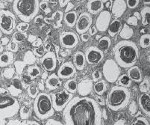

Предположительно, генетический дефект приводит к нарушению обменных процессов и снижению синтеза альвеолярной жидкости, гиперпродукции и накоплению белка в лёгочных альвеолах и бронхиолах. Этот белок пропитывается солями кальция и образует микролит (конкремент размером 0,3-2мм). Альвеолярный просвет наполовину и более заполняется микроконкрементом. Процесс постепенно поражает всю лёгочную паренхиму. Лёгкие становятся каменисто-плотными и тяжёлыми. Нарушается альвеолярный кровоток и газообмен. Развивается дыхательная недостаточность.

При патоморфологическом исследовании выявляется повышение плотности лёгочной ткани в базальных и средних отделах. Иногда вес лёгких может достигать 4-х килограммов. В просветах альвеол и бронхиол обнаруживаются микролиты сложного концентрического строения. В составе мельчайших конкрементов выявляются карбонаты и фосфаты кальция, а также магний, цинк, натрий, медь и другие микроэлементы. В интерстициальной ткани лёгких определяются признаки фиброза.

• Биопсия лёгкого. Основной метод верификации диагноза. Выполняется при проведении бронхоскопии или трансторакально. В биопсийном материале обнаруживаются концентрические микроконкременты, расположенные в альвеолах, просветах бронхиол и мелких бронхах. В стенках бронхов определяется избыточное отложение гранул гликогена.